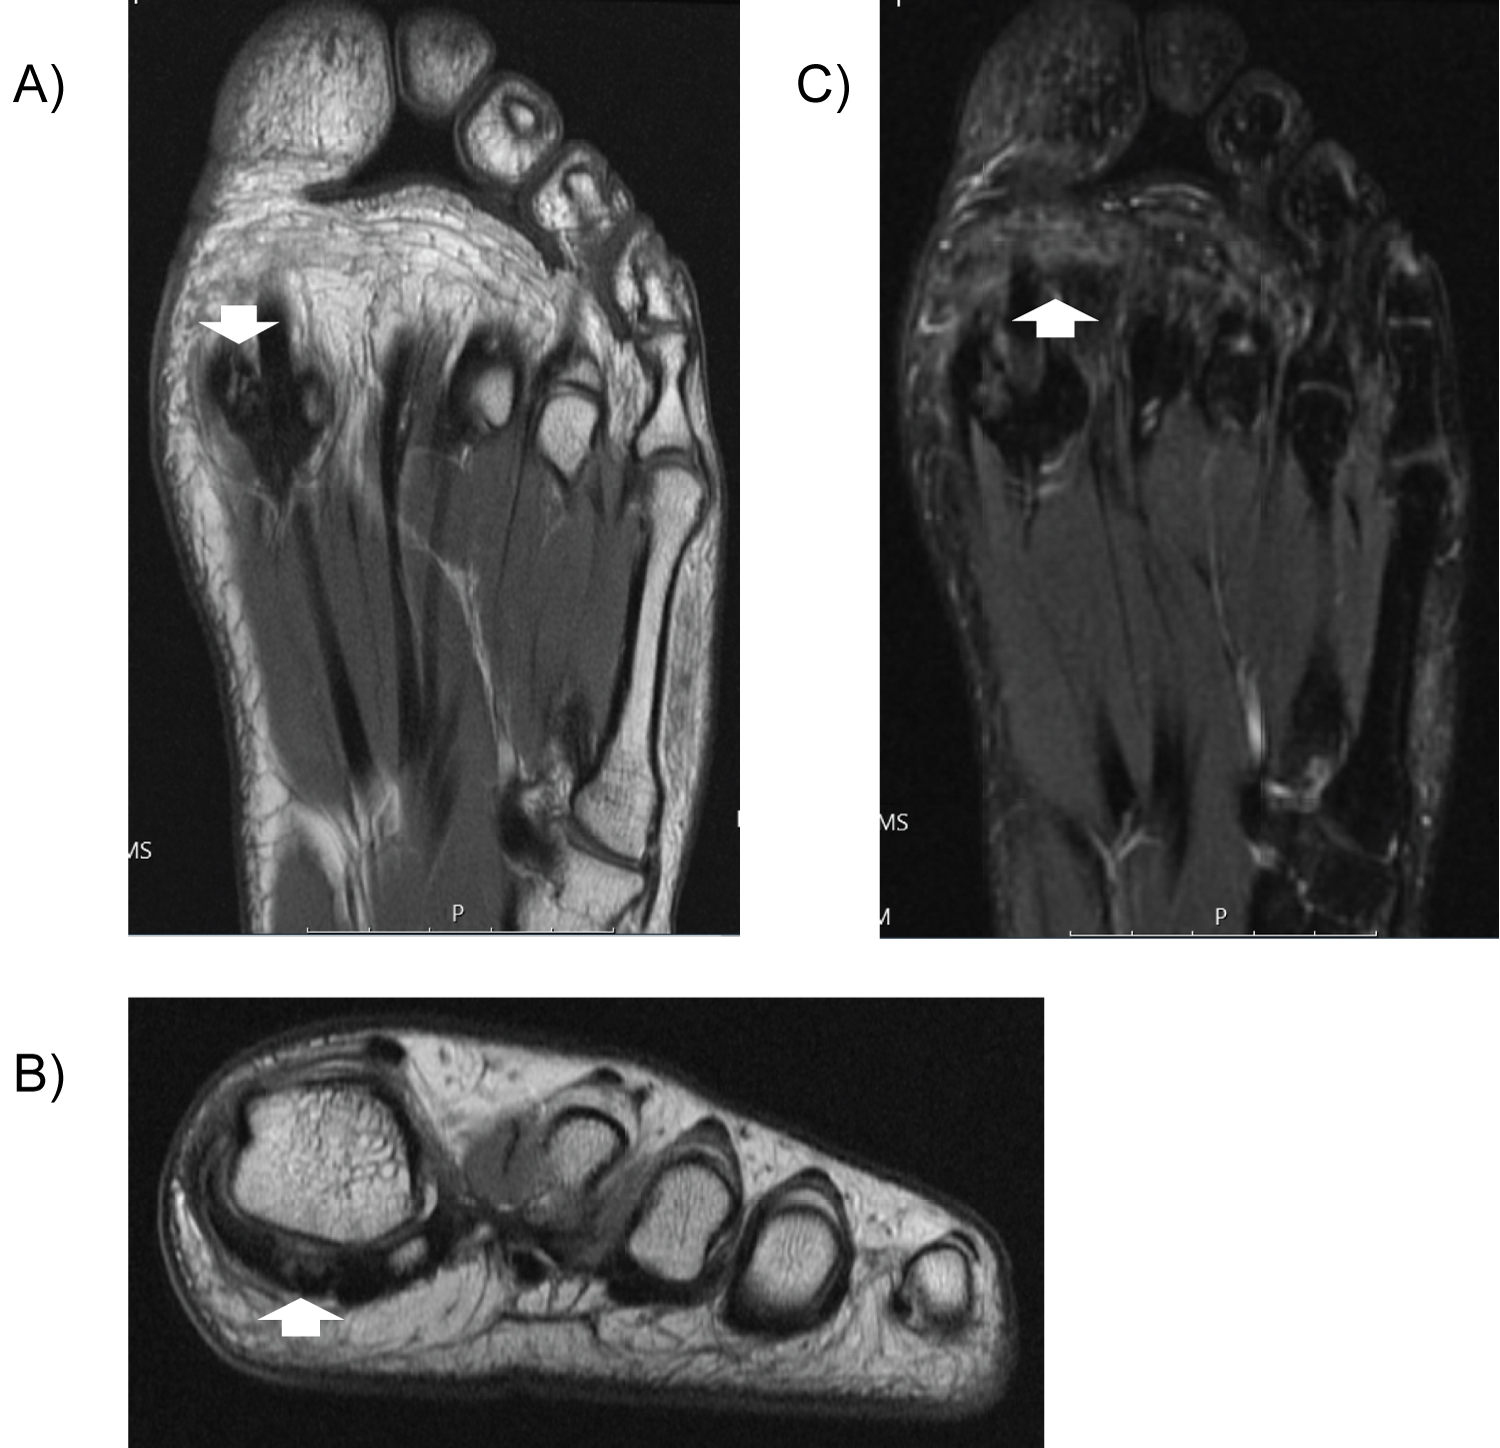

A 19-year-old male squash player presented with first MTP joint pain that began while playing squash two years prior. The pain was rated 4/10, exacerbated by kneeling, walking, and running. He obtained custom orthotics to no relief. Exam revealed tenderness at the medial sesamoid and FHB, full and painless ROM, and full strength. MRI showed fracture of the medial sesamoid and associated synovitis (Figure 5).

Figure 5: Case Three. MRI of the left forefoot (proton density sequence) demonstrates fracture at the medial sesamoid on coronal (a) and axial (b) views (arrows). C) MRI of the left forefoot (inversion recovery) demonstrates edema at medial sesamoid (arrow). View Figure 5

At two weeks post-injection, he reported 1/10 pain. By six month follow up, he completed PT and endorsed 60-70% improvement overall (pain-free most days but occasional monthly flares without adherence to HEP).